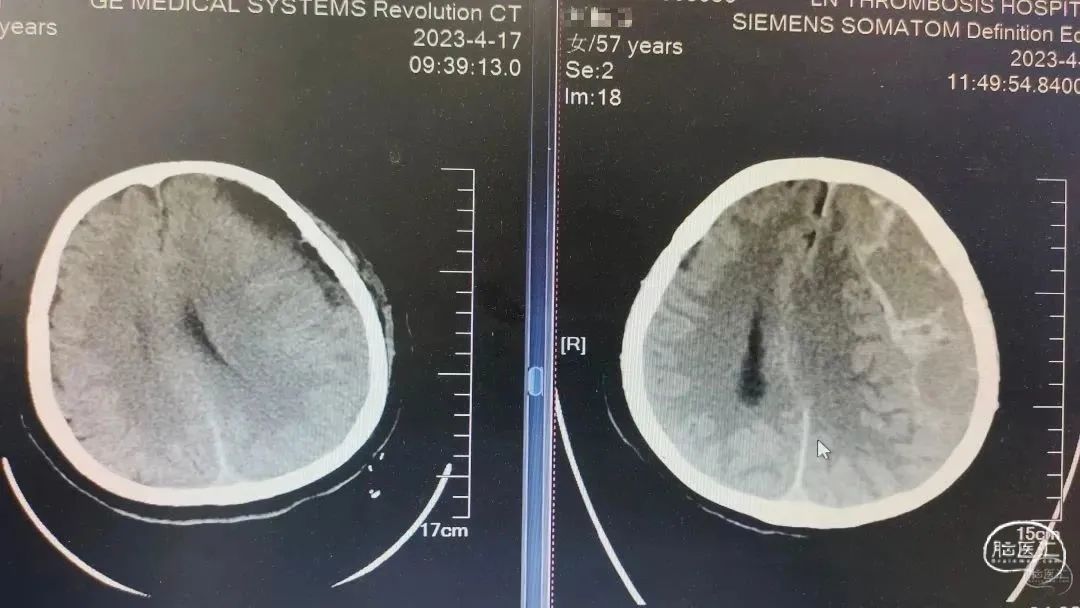

术前CT

患者双侧亚急性硬膜下血肿,血肿混杂密度,神经内镜下血肿清除术。